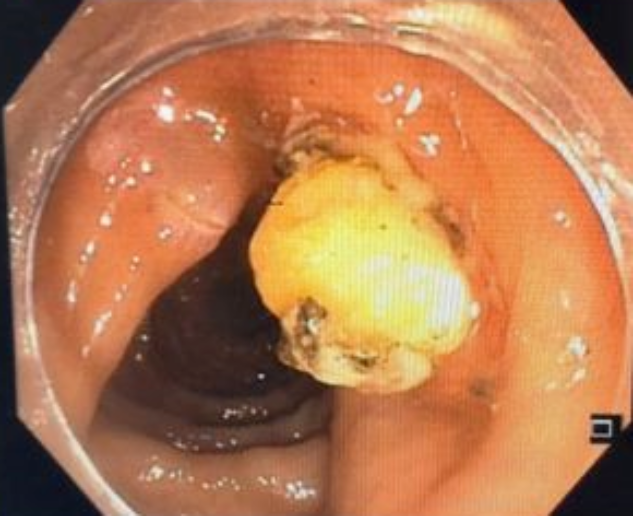

胃肠科消化专家宋国彬经过胃肠镜检查发现刘先生距离肛门50cm处可见一约1.2cm脂肪瘤,病情较为复杂, 胃肠科团队经过详细的病情评估,与家属充分沟通后,为患者刘先生制定了ESD微创手术******方案。

术前

胃肠科手术室内消化专家宋国彬与护士姜士秀的紧密配合按照计划顺利实施手术,在粘膜下注射生理盐水2ml,粘膜切开刀环周切开,剥离后暴露瘤体,完整剥离后置3枚和谐夹缝合创面,历时2个小时的手术,术程顺利,无出血及穿孔。